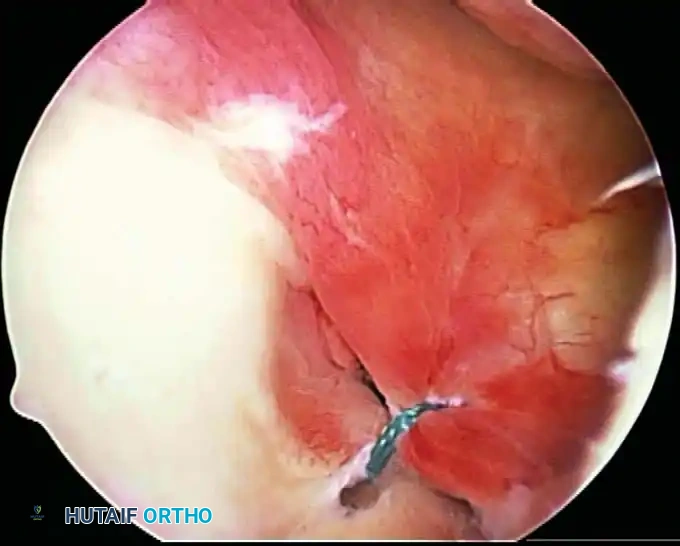

Once diagnostic evaluation is complete and hemostasis is secured, the therapeutic phase commences. Whether performing a SLAP repair, a Bankart stabilization, or a rotator cuff repair, the principles of tissue mobilization, anatomical footprint restoration, and secure biomechanical fixation remain paramount.

Modern arthroscopy relies heavily on suture anchors (biocomposite or all-suture constructs) and advanced arthroscopic knot-tying or knotless techniques. The ability to pass sutures through retracted, fibrotic tissue and secure them under appropriate tension without strangulating the microvascular supply is the hallmark of a master arthroscopist.

* Instability/Labral Repairs: Immobilization in a sling (often with a small abduction pillow) for 4 to 6 weeks. External rotation is strictly limited to protect the anterior capsulolabral repair.